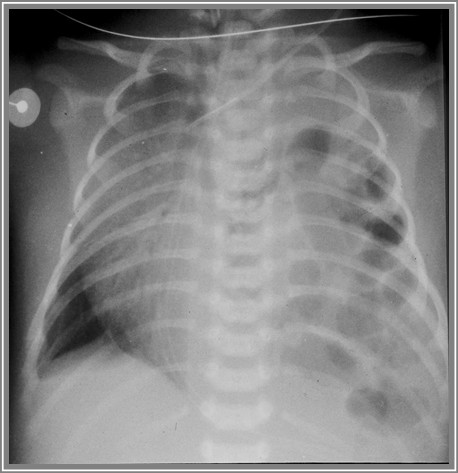

Poniższe zdjęcie rtg klatki piersiowej u noworodka przedstawia obraz typowy dla: